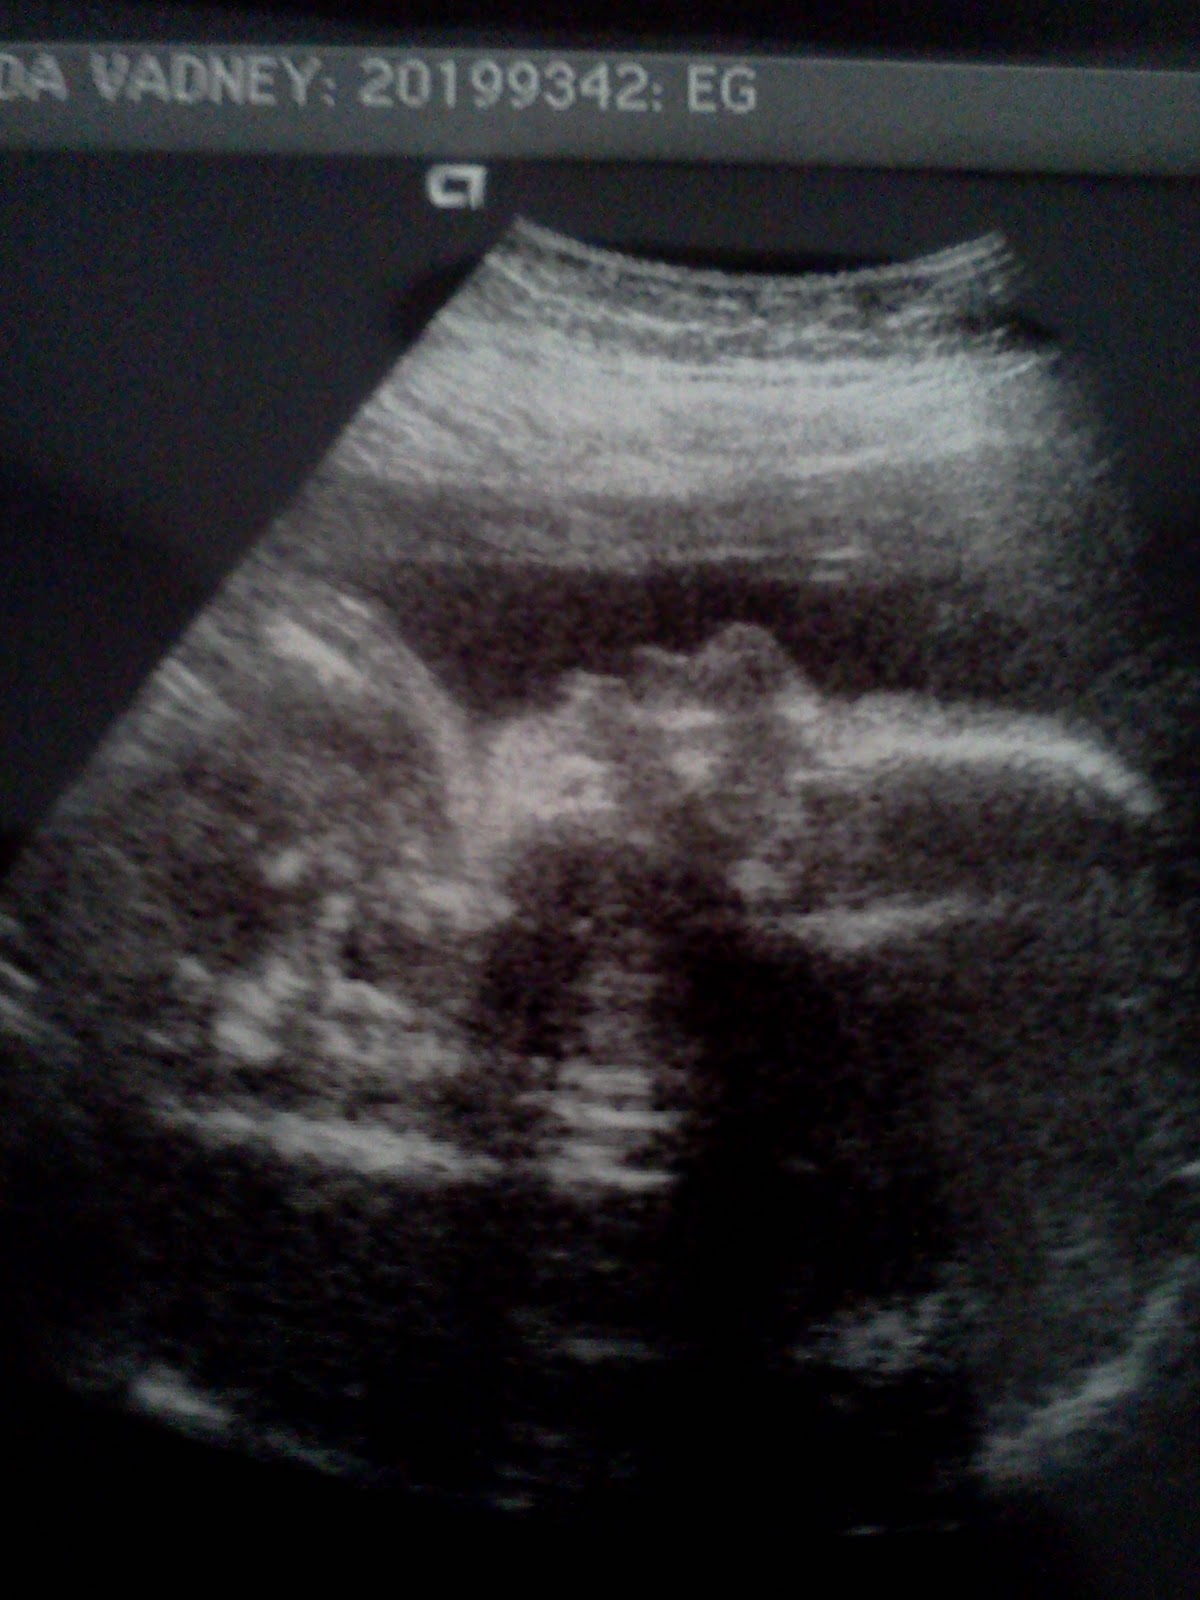

This is a picture of her perfect heart. You can see all four chambers. This little heart has mommy and daddy's heart!

Friday we went in for our second anatomy scan because our little angel was being stubborn the first time around at week 18. Tech got all the shots she needed we are assuming as she did not mention that Mya was being uncooperative as it has been mentioned many times before. J The ultrasound tech sent us home with a few awesome pictures of Mya. One of which is a picture of her heart which she said is as perfect as can be. I love that you can see all four chambers clearly. And it is even more amazing in the ultrasound to see that little heart beating so perfectly in rhythm.